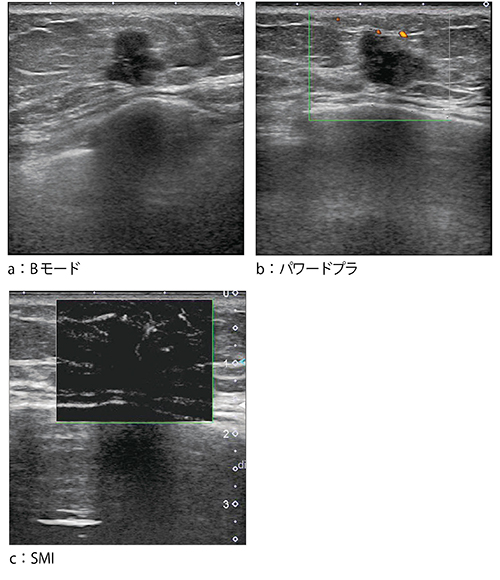

●症例1:浸潤性乳管癌(31歳)

症例1は,超音波検診にて右乳房に腫瘤性病変が指摘された。Bモードでは,乳腺の中に認められる腫瘤で,後方エコーが増強していた(図3 a)。パワードプラでは,腫瘤は比較的大きいものの,中を貫くような血流がうまく描出されず,血流が不連続に点在していた(図3 b)。しかし,SMIでは,腫瘤の内部へと続く連続した血流が明瞭に描出されている(図3 c)。SMIは白黒表示だけでなく,カラー表示も可能である(図3 d)。SMIを適用することで,従来見えなかった血流が見えるようになったとの印象を持った。

図3 症例1:浸潤性乳管癌(31歳)